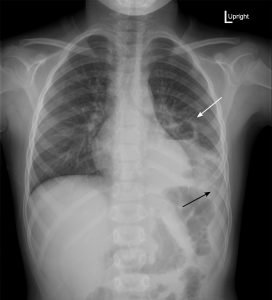

Upright posterior-anterior plain chest films show a left lower lobe consolidation with an air-fluid level and a single septation consistent with a pulmonary abscess (white arrows). A small left pleural effusion was also present, seen as blunting of the left costophrenic angle and obscuration of the left hemidiaphragm (black arrows).

Pediatric pulmonary abscesses are rare, most commonly caused by aspiration, and the majority consequently arise in dependent portions of the lung.1 The most common pathogens in children are Streptococcus pneumoniaeand Staphylococcus aureus.1 Immunocompromised patients and those with existing pulmonary disease more commonly contract Pseudomonas aeruginosaor Bacteroides, and fungal pathogens are possible.1 Common symptoms include tachypnea, fever, and cough. Imaging is necessary to distinguish pulmonary abscesses from pneumonia, empyema, pneumatocele, and other etiologies.

Plain film radiography may miss up to 18% of pulmonary abscesses yet is often the first modality to visualize an intrathoracic abnormality.2 If seen, pulmonary abscesses most often appear as consolidations with air-fluid levels. Generally, pulmonary abscesses are round with irregular, thick walls, whereas empyemas are elliptical with smooth, thin walls.3 However, these characteristics cannot definitively distinguish these processes.2 Advantages of plain films include being low cost and easily obtained. Computed tomography (CT) of the chest with contrast has 100% sensitivity for pulmonary abscess and empyema but is more expensive and less frequently available.